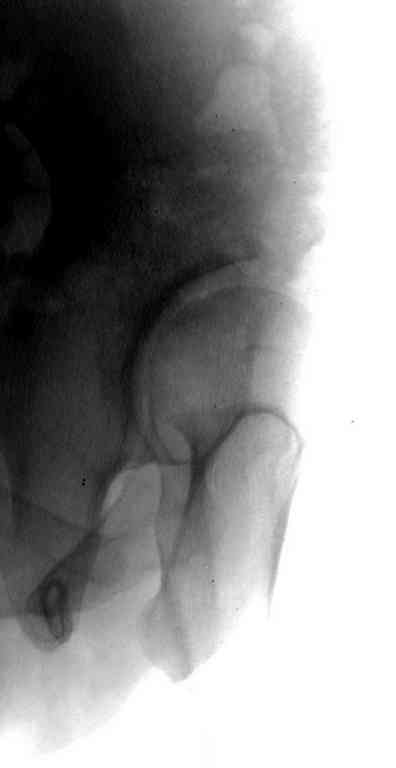

Представляю Р-снимки: обзорная, с отведением и с приведением.

Глубокоуважаемый Абдурашид. Здесь нет снимка с отведением. Если Вы сами сходили в рентгенкабинет и лично отвели пораженную конечность максимально возможно, а также дали максимально возможную внутреннюю ротацию-это одно!!!! Значит у пациентки тяжелейшая приводящая контрактура тазобедренного сустава!! И необходимо разобраться-миогенная или артрогенная? Если же Вы просто назначили указанный снимок и доверили произвести укладку рентгентехнику-это другое!!! Одному богу известно, что она делала, ведь на р-снимке отведения нет!

Все предыдущие корреспонденты предлагают вам достаточно простую вещь-смоделировать предлагаемую Вами операцию (т.е. дать отведение и внутреннюю ротацию) и посмотреть, как изменятся соотношения в суставе. Не обижайтесь, но судя по представлению клинического случая угловые величины, характеризующие пространственные соотношения в тазобедренном суставе, ваши рентгенологи не считают.

Уважаемый Игорь Владимирович. диссертации М М Камоска, и В Е Баскова я нашел, но почему-то не могу открывать, и еще в данном случае имеется дисплазия т/б за счет недоразвития крыши в/впадины да и всей подвздошной кости, маргинального вывиха или латеропозиции головки вследствие лечебных ощибок нет, головка стоит на месте. Р-граммы сделал сам, но почему-то у больной отведение и внутренная ротация стали очень болезненной, и сухожилия приводящих мышц сильно натягивается.(контрактура артро-миогенная).